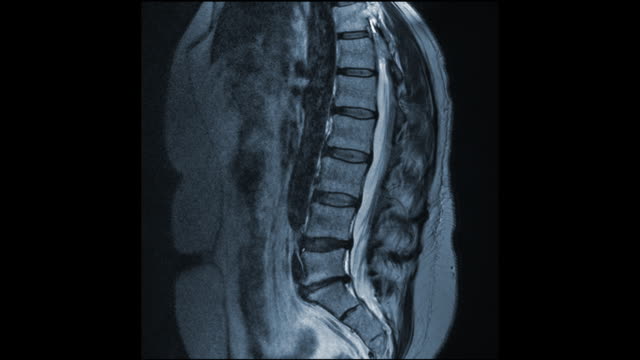

요추 전만은 허리디스크 치료와 예방에서 핵심적인 역할을 합니다. 요추 전만을 만들면 디스크의 압력이 감소하고 허리디스크 증상을 완화할 수 있습니다. 이를 위한 두 가지 자세가 있습니다.

척추의 모양은 S자형이며 요추의 중립 자세는 C자형입니다. 그러나 햄스트링이 단축되면 골반이 뒤로 넘어가게 되어 후방경사 상태가 되며, 이로 인해 요추 전만이 감소합니다. 햄스트링이 항상 단축되어 있는 상태에서 요추 전만 자세를 유지하려고 하면 척추 근육과 인대에 부하가 증가하고, 결과적으로 척추 관절의 불안정성과 통증의 원인이 될 수 있습니다.